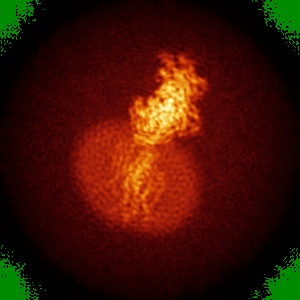

Cryo-EM structure of human GABA(B) receptor bound to the positive allosteric modulator rac-BHFF

Sample: Gamma-aminobutyric acid type B receptor

Fitted models: 7ca3